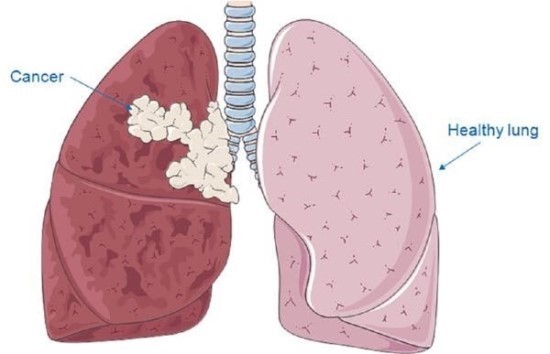

폐암 초기증상 11가지 특징

폐암은 위암, 갑상선암 다음으로 3번째로 발병 빈도가 높은 3대 암 중 한 가지인데요. 폐암은 재발과 전이까지의 빈도도 잦은지라 완치가 어렵다고 하며 폐암 발병 초기에는 거의 증상이 없을 수